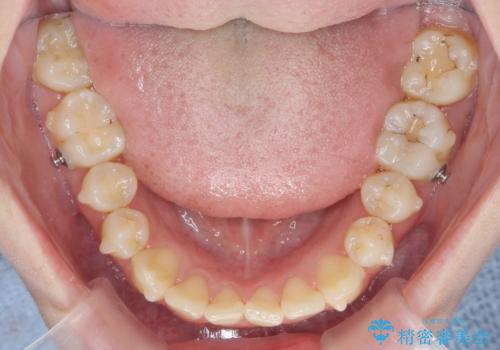

- 前歯の角度 奥歯の噛み合わせの改善をするために、矯正治療を希望され来院されました。

右側奥歯は上顎が相対的に前方に位置し(上顎前突)、そのため前歯の角度も突き出たようになり出っ歯のように見える状態でした。

マイクロインプラントを用いて、上顎奥歯を後方に移動させることで噛み合わせ・前歯の角度を改善していきます。

少し時間はかかりましたが、しっかりと綺麗な歯並びに仕上げることができ、大変喜んでいただくことができました。